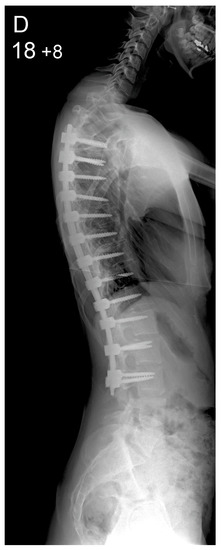

Figure 2.

Patient aged 15 years and 9 months with a right thoracic AIS producing thoracic translocation and listing of the trunk to the right, as well as a lordotic thoracic spine causing spinal penetration into the chest, partial bronchial obstruction and right lower lobe atelectasis (A,B). The patient underwent posterior scoliosis correction using the HS technique which restored segmental and global coronal/sagittal spinal balance at latest follow-up (age 19 years and 2 months) into adult life (C,D). Clinical photographs demonstrate excellent correction of the coronal deformity and associated rib hump after scoliosis surgery (E–H).